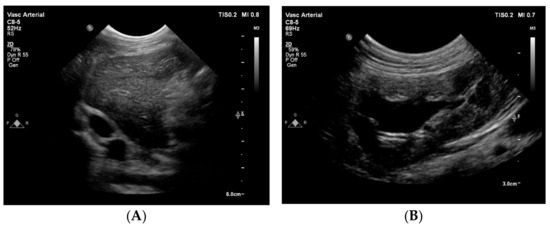

Three weeks after the initial visit, a non-selective angiography and a CT scan were performed under general anesthesia. For premedication, butorphanol (0.6 mg/kg; Dolorex 10 mg/mL MSD Animal Health, Boxmeer, The Netherlands) was administered intravenously. For anesthetic induction and maintenance, propofol (PropoVet 10 mg/mL, Zoetis BV, Capelle aan den IJssel, the Netherlands) was administered intravenously as a variable rate infusion. For the non-selective venogram, an over-the-needle catheter (18 gauge, 1.3 × 45 mm, B-Braun, Melsungen, Germany) was placed into the right saphenous vein and 7 mL iodinated contrast material (1 mL/kg iobitridol 768 mg/mL, 350 mg iodin/mL, Xenetix 350, Guerbet, Villepinte, France) was injected manually. The contrast material in the CVC did not flow more cranial than the level of the first lumbar vertebra (Figure 5A).

After removal of the stent delivery system, the angiographic catheter was reintroduced over the guidewire. After removal of the guidewire, an angiogram was performed with machinal injection of 7 mL of iodinated contrast agent (10 mL/sec, 1000 PSI). The angiogram showed a good positioning of the stent, where approximately 1 cm of the stent was positioned in the aneurysm (Figure 5B and 7B). There was a fast clearance of contrast with a good cranially directed flow in the CVC and azygos vein (Figure 5B). However, some contrast remained in the segment of the azygos vein where the stent was positioned for at least 20 s (Figure 7B). Inspiration facilitated blood flow in the azygos vein into cranial direction towards the heart. Invasive pressure measurement via the side-port of the introducer showed a mean pressure of 8 mmHg. After removal of the catheter and introducer, the skin incision was closed with a purse string suture. An intravenous dose of heparin (100 IU/kg) was administered. Postoperative radiographs were made to document the position and shape of the stent (Figure 8).

Figure 5. Non-selective venography before (A) and after (B) stenting of the azygos vein. With the dog in lateral recumbency, manual injection of iodinated contrast material was performed via the saphenous vein. A sizing catheter is located in the esophagus. (A) The caudal vena cava cannot be followed more cranial than the level of the first lumbar vertebra, and the dye does not reach the heart. (B) After stent implantation into the azygos vein at the level of the diaphragm, the dye reaches the heart. The contrast column flows through the aneurysmal dilatation of the azygos vein and reaches the intrathoracic part of the azygos vein. A stent guide is located under the dog.